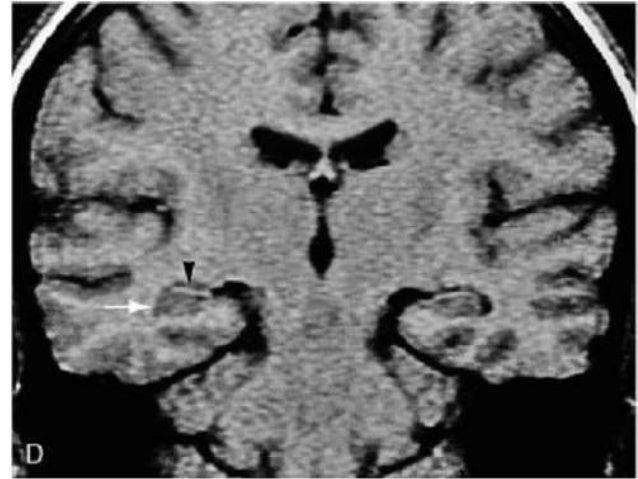

The head (1) is located in front of the mesencephalon, the body (2) can be found at the level of the mesencephalon and the tail (3) is posterior to the mesencephalon. To easily recognize the different portions of the hippocampus, we can use the mesencephalon (4). 1 = hippocampal head, 2 = hippocampal body, 3 = hippocampal tail, 4 = mesencephalon, 5 = amygdala, 6 = hippocampal digitations, 7 = temporal horn of the lateral ventricle, 8 = uncal recess of the lateral ventricle, 9 = splenium of the corpus callosum, 10 = subsplenial gyri, 11 = crura of the fornices. The hippocampal body is shown in detail in Fig. Zoomed-in 3-T coronal T2-weighted images at the level of the hippocampal head ( c) and the hippocampal tail ( d).